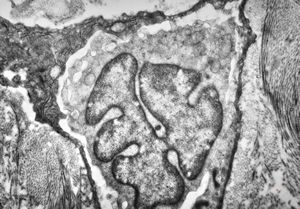

F, 37y. | mycosis fungoides … cerebriform nucleus of Sézary cell